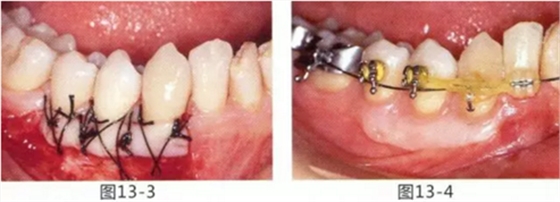

圖14-7 配戴最終修復(fù)體完成5年后的狀態(tài)。保持良好。